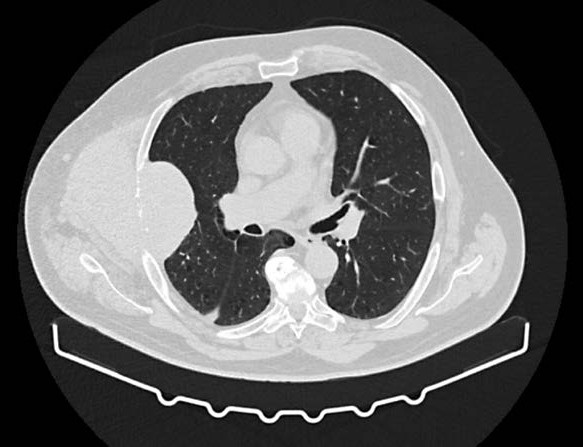

• Community-Acquired Necrotizing Pneumonia due to Panton-Valentine Leukocidin-Producing Methicillin-Sensitive Staphylococcus aureus

Vitor Mendes, Patrícia Moniz, Pedro Póvoa

172-177

DOI: https://doi.org/10.60591/crspmi.455